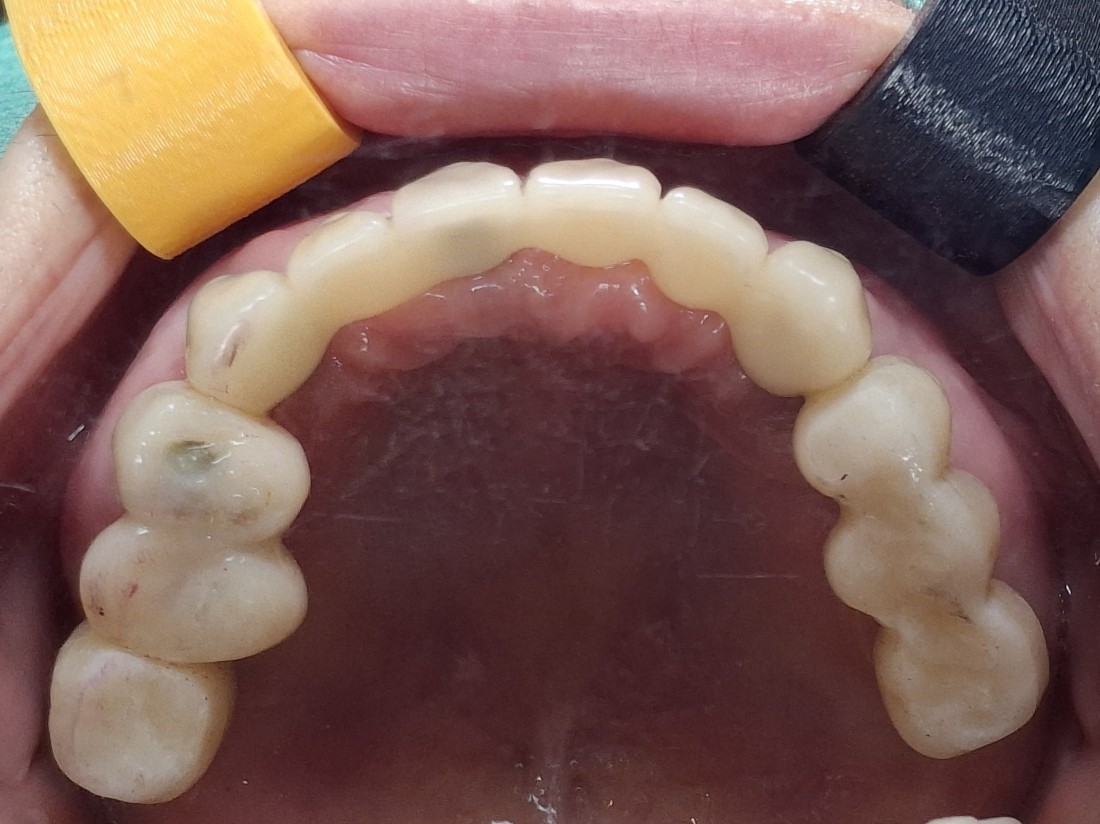

광주 상악임플란트 치과는

전체 임플란트 수술도

단 2번의 수술만으로

완성합니다.

광주 상악임플란트 치과에서는

위 / 아래 전체 임플란트를

붓기, 출혈, 통증을 최소화할 수 있는

디지털 가이드 임플란트 수술방법으로

단 2번의 수술만으로 완성하고 있습니다.